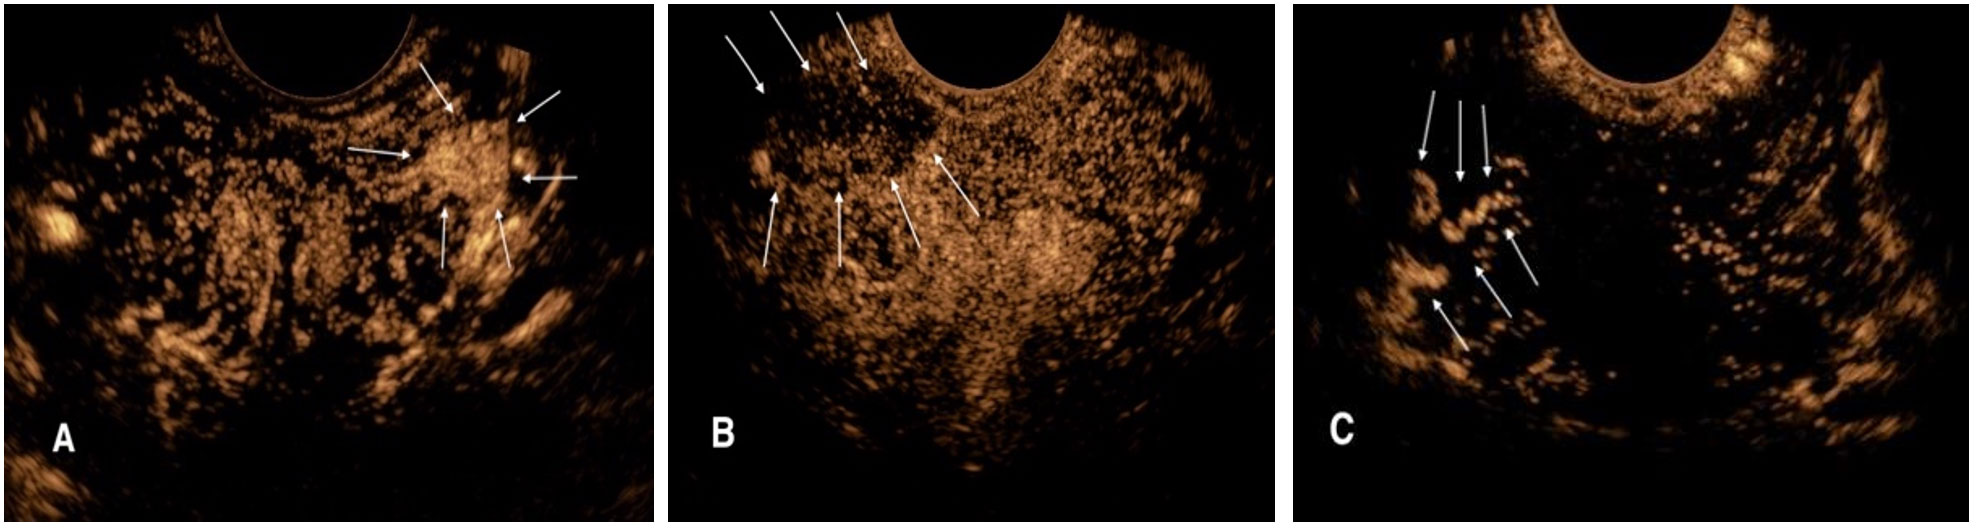

Aims: This study aimed to analyze the consistency between pathology of combined systematic and contrast-enhanced ultrasound (CEUS)-targeted prostate biopsy and radical prostatectomy (RP) by building a nomogram to predict the pathology upgrade of Gleason grade group (GGG). Methods: A total of 113 prostate cancer participants with combined systematic and CEUS-targeted prostate biopsy followed by RP were recruited between January 2021 to November 2024. The Kappa coefficient of pre-and post-RP GGG was calculated. The independent predictors for pathology upgrade were screened using logistic regression, and then applied to build a nomogram for pathology upgrade prediction. The performance of nomogram was assessed by receiver operating characteristic analysis, calibration curve and decision curve analysis. Result: Among 113 participants, 25 (22.1%) Gleason grade group upgrading (GGGU) and 88 (77.9%) non-GGGU were found. Moderate consistency of prostate cancer GGG between combined systematic and CEUS-targeted prostate biopsy and final RP pathology was found (Kappa = 0.46, P < 0.01). The primary biopsy GGG (OR = 0.18, P = 0.01) and greatest percentage of cancer in a single core (OR = 1.04, P < 0.01) were independent predictors for post-RP GGGU. The area under the curve of the established nomogram reached 0.83, and calibration curve showed a robust result. Conclusion: The nomogram integrating CEUS-targeted fusion biopsy variables effectively predicted the risk of pathology upgrade in prostate cancer, which held promising potential to guide clinicians in optimizing the surgical management in prostate cancer patients.